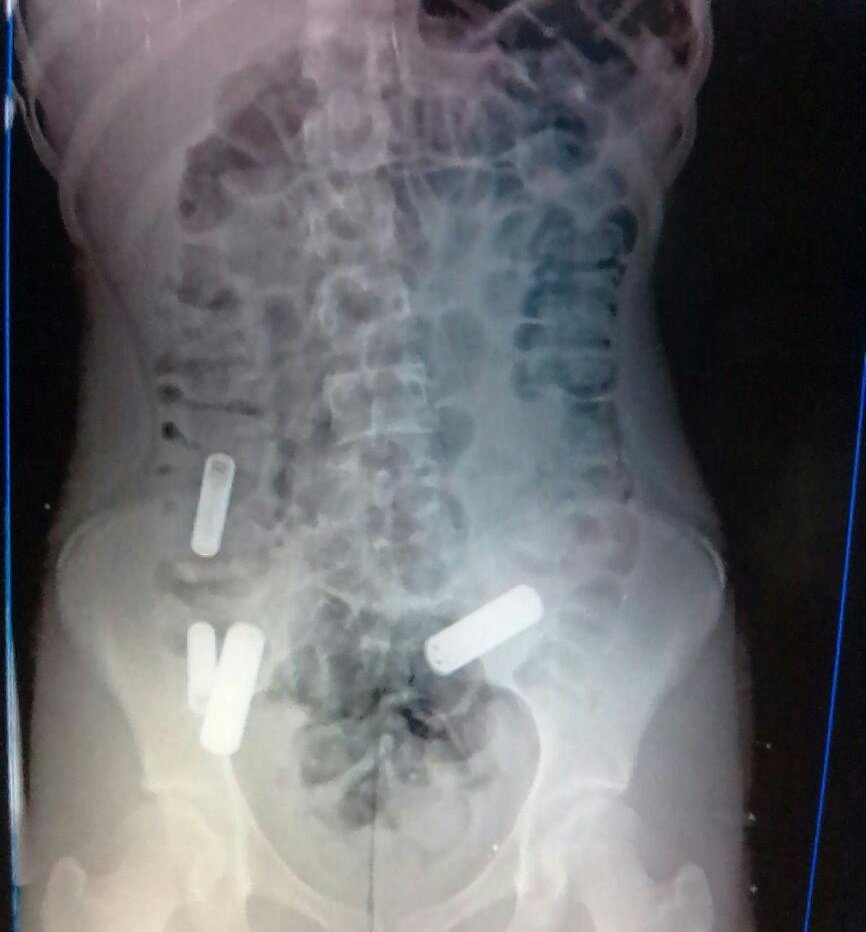

Una adolescente de 13 años fue ingresada este domingo en horas de la tarde al Hospital Dr. Miguel Pérez Carreño, en Caracas, luego de que se tragara unas pilas.

Se conoció extraoficialmente que la jovencita se tragó al menos cuatro pilas porque su madre no la dejó asistir a una fiesta.

Transcendió que los médicos de guardia del hospital le sacaron las pilas por medio de una endoscopia digestiva.